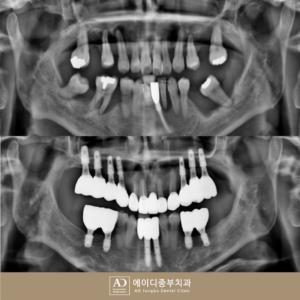

양산수면치과, 만성치주염으로 치아 발치 후 전체임플란트로 회복

양산수면치과, 만성치주염으로 치아 발치 후 전체임플란트로 회복 혹시 칫솔질을 할 때 잇몸에서 피가 나거나, 치아가 시큰거리고 흔들리고, 양치를 해도 입 냄새가 심해지는 느낌을 받아보신 적 있으신가요? 많은 분들이 이러한 증상을 단순히 피로나 일시적인 현상이라 생각하기도 하지만 치주 질환을 의심해 볼 수도 있는데요. 치주 질환은 구강 내에 있던 세균이 치태와 칼슘 더보기…